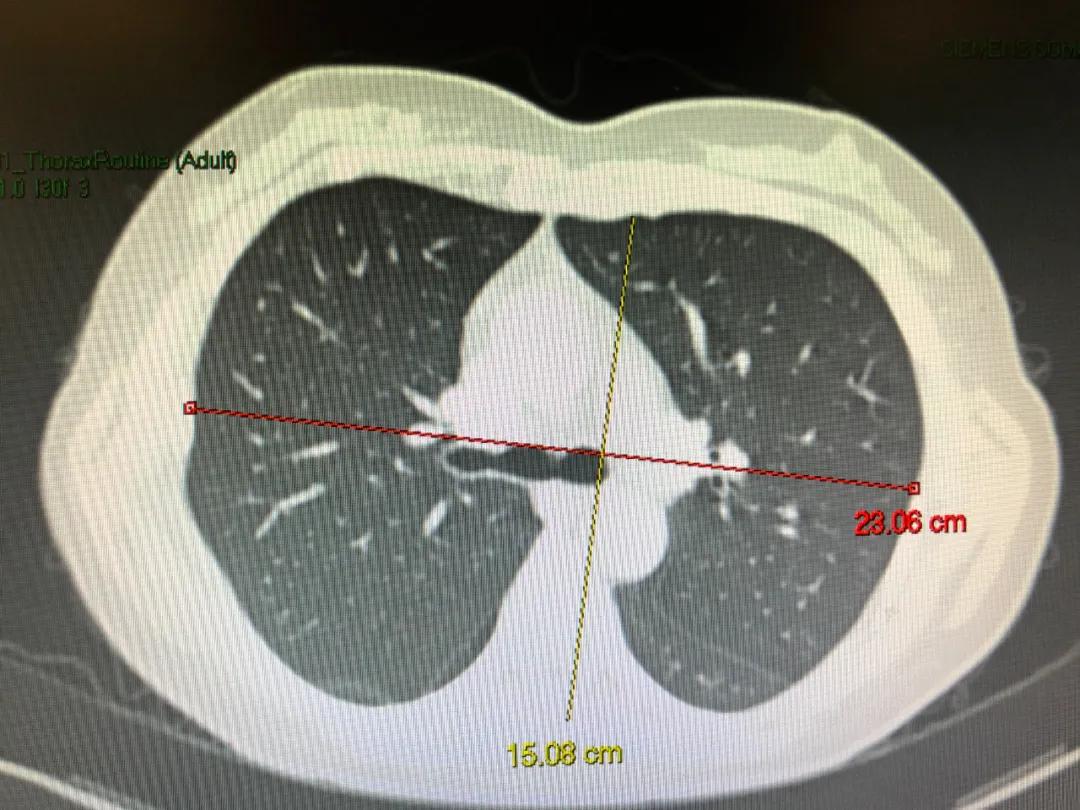

图为正常胸廓,其前后径15,横径23,基本比例为1:1.5

图为重度肺气肿患者的胸廓,其前后径19.18,横径23.9,基本比例为1:1.2